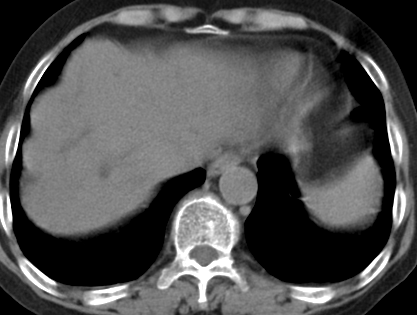

以下是引用齐原在2006-11-8 23:21:00的发言:[br]肝脏体积增大.肝表凸凹不平,肝内胆管扩张,胆总管扩张,胆总管末端突然截断,胰腺勾突增大,形态不规则.胰管扩张.考虑胰头癌.并低位梗阻性胆系扩张,胆囊炎.脾大.建议增强

以下是引用dyqct在2006-11-9 9:14:00的发言:[br]肝大,表面呈波浪状,肝内外胆管扩张,胆总管下端腔内见小结节状等密度影,胰管轻度扩张。胆囊显示不清。[br]考虑:1、胆总管下端占位性病变(等密度结石?壶腹部肿瘤?);[br] 2、肝硬化?[br] 3、建议增强扫描进一步检查。